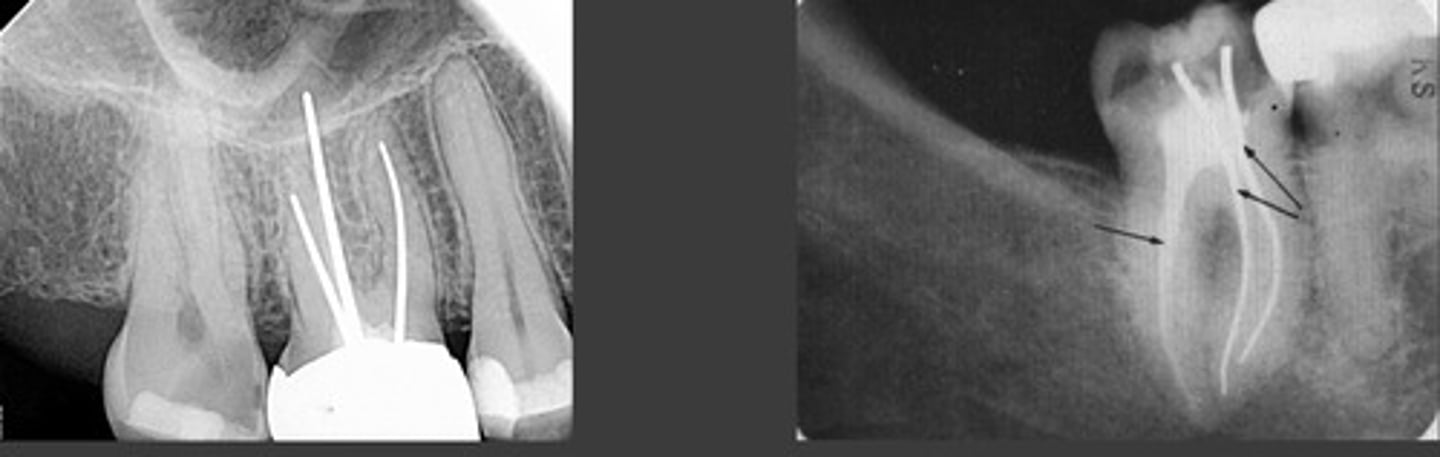

root canal therapy of gutta percha

gutta percha fills root canal

-not as opaque as silver points, diffused

root therapy of silver points